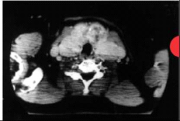

| 13:53, 12 בנובמבר 2012 | תצלוםתריס314.png (קובץ) |  |

100 קילו־בייטים | Motyk | 1 | |